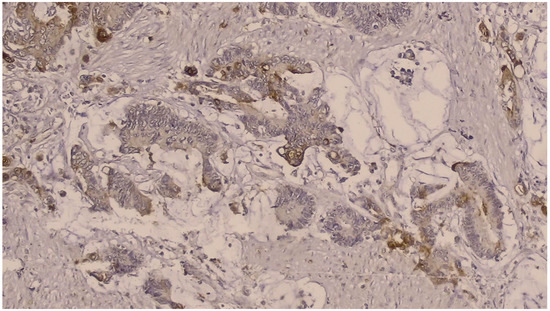

NGAL positivity was defined as diffuse or patchy areas of strong cytoplasmic and/or nuclear staining [Figure 1]. In addition, we counted the number of NGAL positive inflammatory cells that infiltrated the tumors per HPF, which was defined as NGAL positivity in the tumor microenvironment [Figure 2]. KIM-1 positivity was described as diffuse or patchy areas of strong cytoplasmic staining [Figure 3]. Since no tumors with nuclear NGAL expression alone were found, the tumors could not be grouped as nuclear and cytoplasmic expression. For both antibodies, strong focal staining or diffuse but very weak staining visible under a microscope was regarded as KIM-1 or NGAL negativity. Both antibodies were not scored because very weak staining was considered as negative.

Figure 3.

Immunohistochemically strong cytoplasmic KIM-1 positivity was determined in tumor cells (DAB × 200).